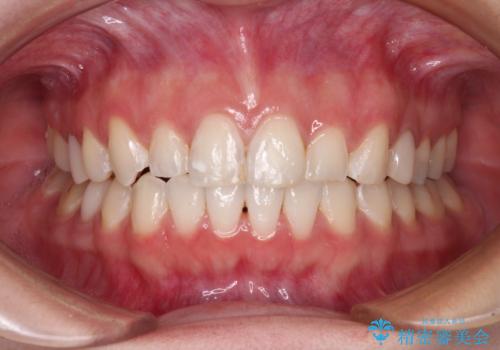

- 2年6ヶ月

インビザラインでの矯正治療を希望されていましたが、奥歯の咬み合わせがインビザライン単独では改善困難と判断されたので、補助装置を併用することとしました。

まずは裏側の装置やワイヤー矯正を用いて歯列幅の狭い上顎を側方に拡大しつつ全体を後方に移動させ、その後インビザラインにて歯列を整えることとしました。

奥歯の咬み合わせの改善は、インビザライン単独では達成しきれないことがあるため、ワイヤー矯正などの補助装置を併用する場合があります。

インビザライン単独の場合と比べ、治療結果は大きく異なります。